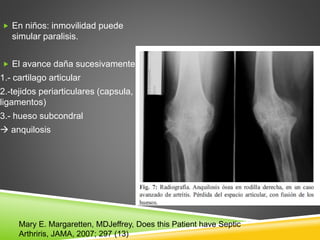

 En niños: inmovilidad puede

simular paralisis.

 El avance daña sucesivamente:

1.- cartilago articular

2.-tejidos periarticulares (capsula,

ligamentos)

3.- hueso subcondral

 anquilosis

Mary E. Margaretten, MDJeffrey, Does this Patient have Septic

Arthriris, JAMA, 2007; 297 (13)